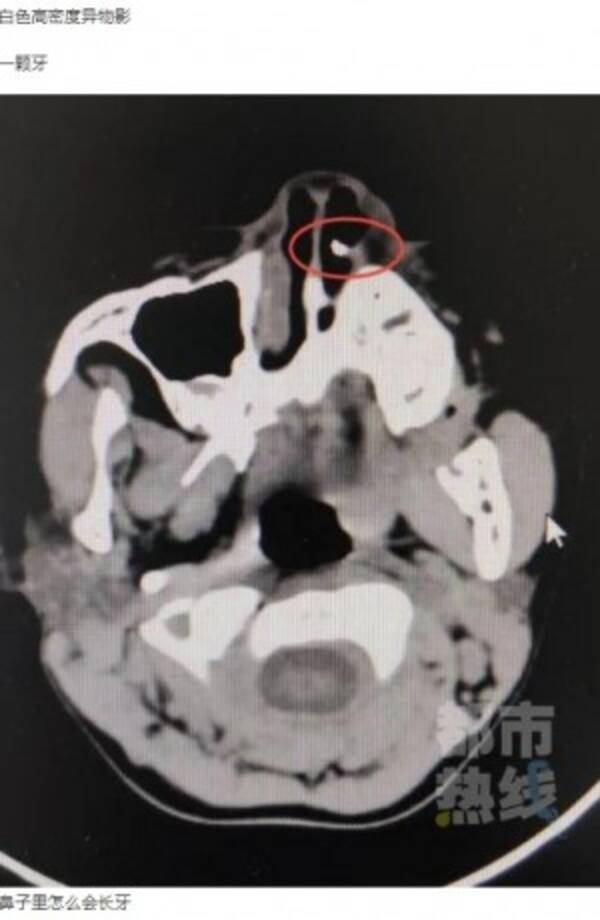

鼻の中に歯が見つかった6歳児 3年前に顔面強打し歯がなくなっていた 中国 年6月28日 エキサイトニュース